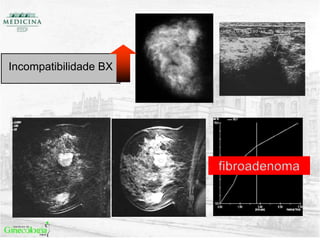

• Incompatibilidade BX

Incompatibilidade BX